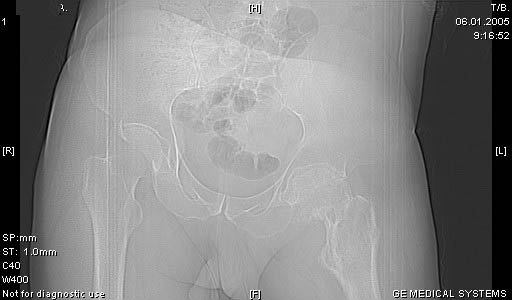

И снова вопрос по эндопротезированию: Пациенту 51 год. Болен с 2000 г, когда отметил умеренные, нараостающие боли в в/3 левого бедра, прогрессирующую контрактуру лев Т/Б сустава.

05.12.04 после падения на бедро боли резко усилились, нога стала неопорной. На рентгенограмме обнаружен патологический перелом шейки бедренной кости. Обследован в отделении костной онкологии. Результат биопсии: асептический некроз проксимального отдела бедренной кости. Вопрос: выбор технологии эндопротезирования - цементная или бесцементная версия. Заранее благодарю! С уважением,А.В.Владзимирский

Проксимальный отдел бедра не виден достаточно на представленных рентгенограммах; но то, что видно, как раз наводит на мысли о цементной фиксации - цилиндрический канал, измененный calcar, кистозные изменения в области большого вертела и т.д.

Как то очень подозрительно выглядит проксимальный отдел бедра для такого очень простого гистологического заключения. Вы уверены, что гистология настолько благополучна и в каком варианте она выполнялась: пункционная или открытая с забором костного блока? Не уверен на все сто , но область проксимального отдела бедра - одно из излюбленных мест для гигантоклеточной опухоли, которая зачастую озлакочествляется (имел два подобных наблюдения). Из своей практики могу сказать, что, к сожалению, информативность пункционной биопсии не сравнима с открытой техникой. Поэтому прежде чем решать цементный или бесцементный протез использовать, я бы повторил биопсию в сочетании со сканированием скелета, сывороточная щелочная фосфатаза, кальций, фосфор сыворотки, СОЭ, С- реактивный белок,

Soglasen s Евгений И Чекашкин, proximal Femur does not look right. Sarcoma? Pagets, Osteomyelitis?. Technicality of the implantaion will be dependent upon underlying pathology, and the surgeon's level of comfort.

Ацетабулум как-то странно выглядит, с дыркой.